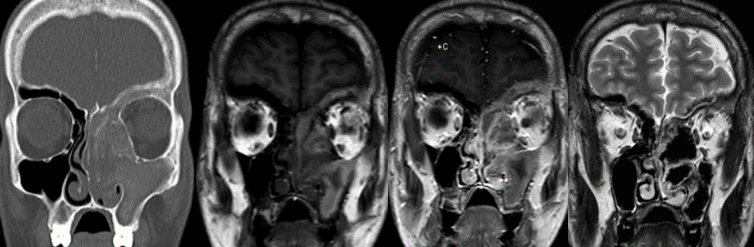

Images of x-rays of skulls

Chronic rhinosinusitis afflicts over 30 million patients in the USA annually, or roughly 12.5% of the population. It has tremendous impacts on the economy and on a patient’s quality of life.  It is defined as symptoms of sinonasal inflammation lasting at least twelve consecutive weeks with corresponding objective physical findings. Symptoms may include nasal obstruction, congestion, nasal drainage, post-nasal drip, facial pressure, loss of smell and/or taste, fever, fatigue, and dental pain. To examine for sinonasal inflammation your physician will use a nasal endoscope to evaluate your nasal cavities and paranasal sinuses. You may also undergo computed tomography (CT) or another form of imaging.